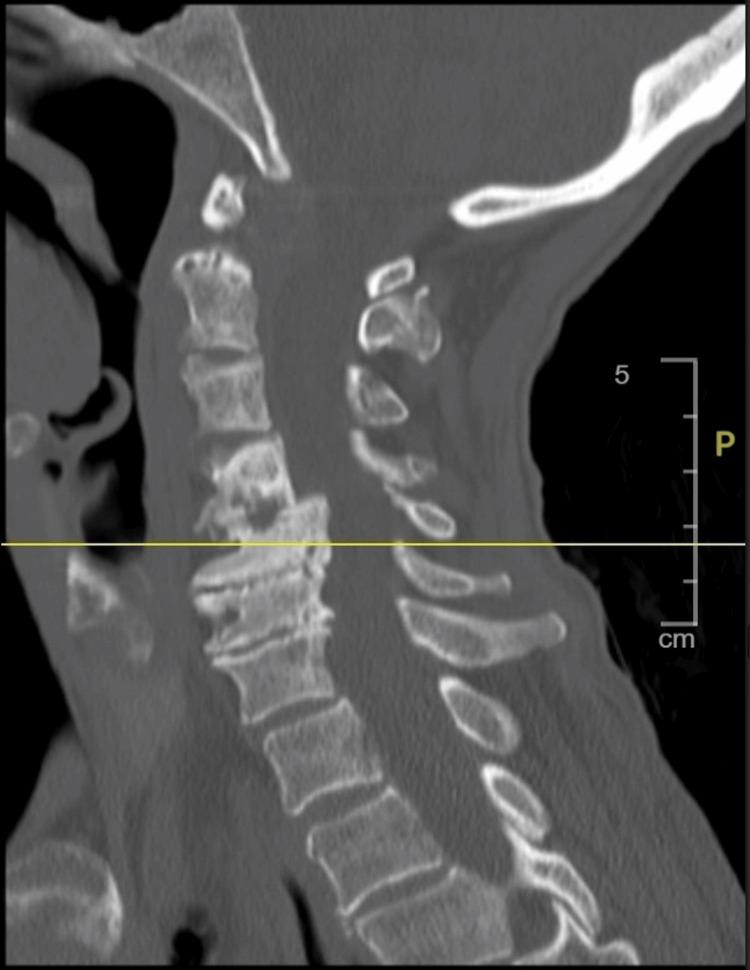

This is the case of a 65-year-old female patient with chronic obstructive pulmonary disease (COPD) who presented following a fall and was found to have a humeral fracture. Initial evaluation showed sepsis of unknown origin, leukocytosis, and elevated inflammatory markers. Persistent abdominal pain prompted imaging studies, which showed multiloculated intra-abdominal abscesses. Ultrasound-guided drainage yielded . Antibiotics, along with percutaneous drainage, resulted in a good clinical response. Follow-up imaging revealed a decrease in the abscess size, with no evidence of a fistula. This case highlights the diagnostic challenges of intra-abdominal abscesses and the importance of timely imaging in patients presenting with sepsis and nonspecific symptoms.

这是一名65岁患有慢性阻塞性肺疾病(COPD)的女性患者的病例,她在跌倒后就诊,被发现有肱骨骨折。初步评估显示有不明原因的脓毒症、白细胞增多和炎症标志物升高。持续的腹痛促使进行影像学检查,结果显示有多处腹腔内脓肿。超声引导下引流取得了……抗生素联合经皮引流产生了良好的临床反应。后续影像学检查显示脓肿大小减小,没有瘘管的迹象。该病例突出了腹腔内脓肿的诊断挑战以及对出现脓毒症和非特异性症状患者进行及时影像学检查的重要性。